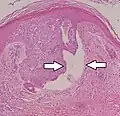

| Squamous-cell carcinoma of the skin | Squamous-cell carcinoma of the skin is generally distinguishable by for example relatively more cytoplasm, horn cyst formation, and absence of palisading and cleft formations. Yet, a high prevalence means a relatively high incidence of borderline cases, such as basal-cell carcinoma with squamous cell metaplasia (H&E stain at left in image). BerEP4 staining helps in such cases, staining only basal-cell carcinoma cells (right in image). | ![]() |